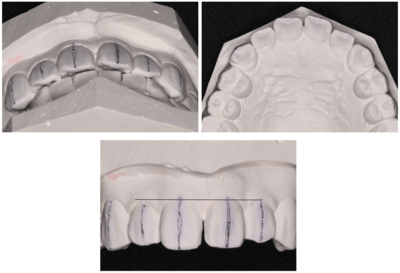

症例③

※最新の料金については、直接医院へご確認をお願いいたします。

前歯をきれいにしたい

| 年齢・性別 | 52歳・女性 |

|---|---|

| 主訴 | 前歯をきれいにしたい |

| 治療内容 | 右上1左1コア形成、仮歯作成、ジルコニアボンドクラウン形成 |

| 治療費 | 合計335,500円(2022年4月現在) 仮歯 2,500円×2 ジルコニアボンドクラウン 165,000円×2 |

| 治療期間 | 2ヶ月 |

| 治療のリスク・副作用 | 天然歯より硬いので嚙み合う歯が欠けてしまうことがある。 セルフケアを怠ると被せ物の内側が虫歯になることがある。 |

治療前

治療後